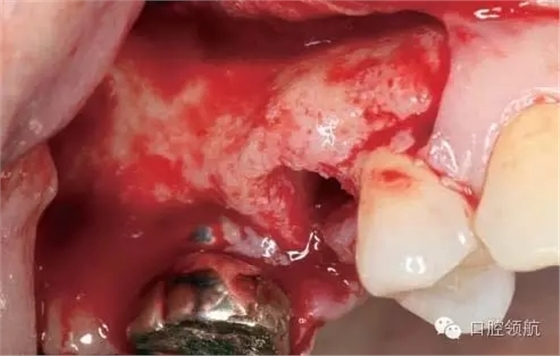

術(shù)前口內(nèi)未見種植體周圍有炎癥等異常表現(xiàn)(圖2),翻開黏骨膜瓣后,10年前手術(shù)入路的痕跡在頰側(cè)骨面已經(jīng)觀察不到了(圖3)。

圖3 黏膜剝離后的口內(nèi)像。10年前手術(shù)入路的痕跡在頰側(cè)骨面已經(jīng)看不到。

采取常規(guī)的上頜竇頰側(cè)壁開窗法,提升上頜竇黏膜,在( 左上第六顆牙)位置突入上頜竇內(nèi)的種植體表面的竇黏膜要非常小心地一點點剝離(圖4)。

圖4 采取側(cè)方入路提升上頜竇黏膜。毫無損傷地將覆蓋種植體表面的黏膜非常小心地一點點地剝離。